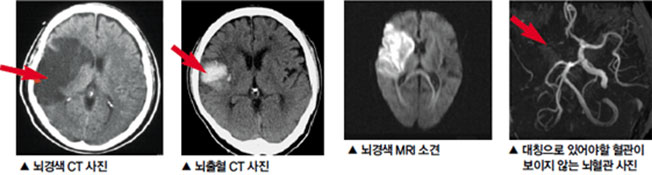

먼저, 뇌경색이 무엇인지에 대해 간단히 설명드리겠습니다. 뇌경색은 뇌에 공급되는 혈액이 차단되어 뇌세포가 손상되는 상태를 의미합니다. 대개 두 가지 종류가 있으며, 하나는 혈전으로 인한 허혈 뇌경색이고, 다른 하나는 출혈로 인한 뇌출혈입니다. 이 두 가지 모두 뇌에 큰 영향을 미치며, 생명을 위협할 수 있는 심각한 질환입니다.